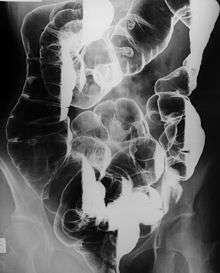

Peutz–Jeghers syndrome (often abbreviated PJS) is an autosomal dominant genetic disorder characterized by the development of benign hamartomatous polyps in the gastrointestinal tract and hyperpigmented macules on the lips and oral mucosa (melanosis).[1] This syndrome can be classed as one of various hereditary intestinal polyposis syndromes[2] and one of various hamartomatous polyposis syndromes.[3] It has an incidence of approximately 1 in 25,000 to 300,000 births.[4]

- Hamartomatous polyps in the gastrointestinal tract. These are benign polyps with an extraordinarily low potential for malignancy.

The risks associated with this syndrome include a strong tendency of developing cancer in a number of parts of the body.[9] While the hamartomatous polyps themselves only have a small malignant potential (<3% - OHCM), patients with the syndrome have an increased risk of developing carcinomas of the pancreas,[10] liver, lungs, breast, ovaries, uterus, testicles and other organs.

Resection of the polyps is required only if serious bleeding or intussusception occurs. Enterotomy is performed for removing large, single nodules. Short lengths of heavily involved intestinal segments can be resected. Colonoscopy can be used to snare the polyps if they are within reach.